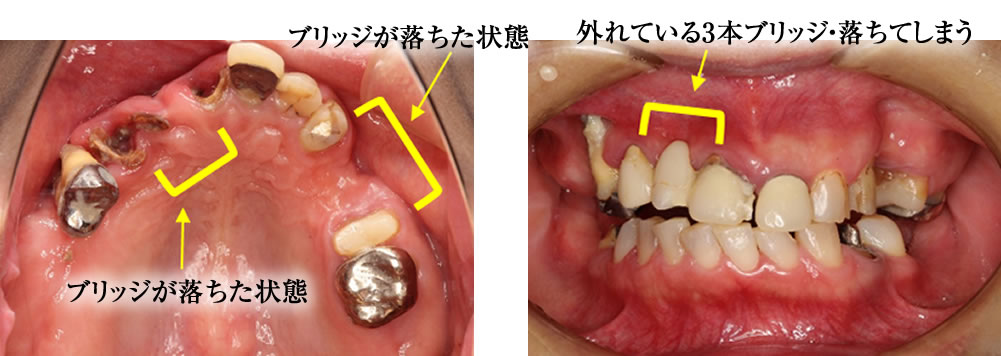

【①初診時】2年前ブリッジが取れたが体調が悪くて治療に行けず、どんどん状態が悪くなった。(40代女性)

初診時の状態 【患者さんの訴え】 かかりつけの歯科医院には、何十年も毎月治療に通っていろいろな治療をしてきた。痛い部位があって訴えても、その部位の対応は何もせず、他の部位の治療ばかりしていた。 治療をしても、次々と悪くな […]

【②緊急対応編】2年前ブリッジが取れたが体調が悪くて治療に行けず、どんどん状態が悪くなった。(40代女性)

緊急対応編 ※この患者さんの治療は、段階を踏んで行ったため、以下の3つに分けて詳細を掲載しています。 【初診時の状態】詳細はこちら>> 【緊急対応編】※本ページ掲載 【義歯治療編】詳細はこちら>> […]